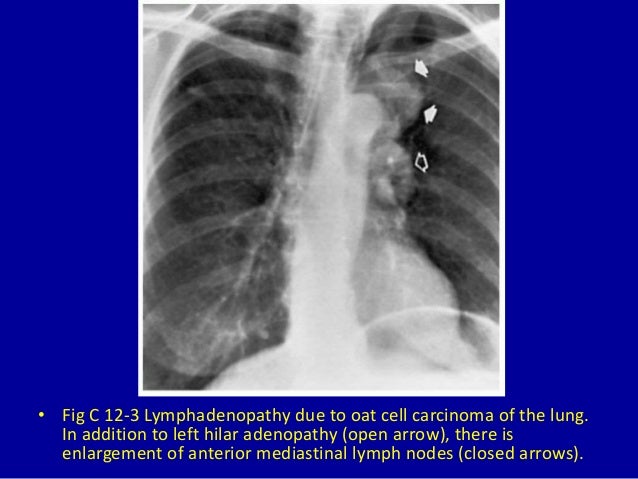

mediastinal lymph node enlarged